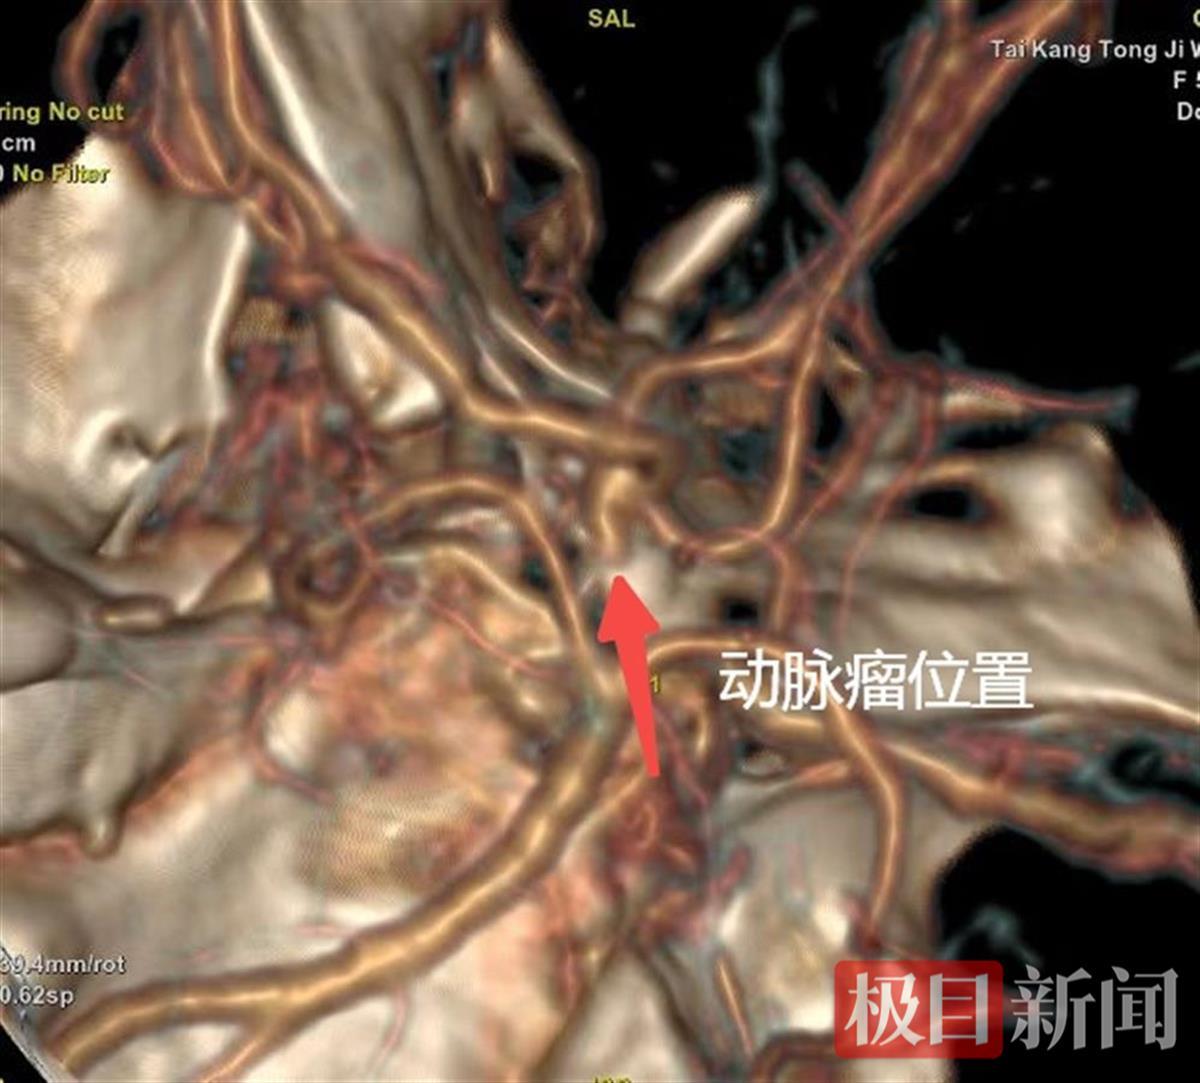

极目新闻通讯员 聂盼 周朕。女子颅内的动脉瘤决裂,生命垂危,泰康同济武汉)医院神经外科专家团队依托“脑血管病一站式一体化救治系统”,分秒必争手术。现在,患者已脱离生命危险,恢复状况杰出。5月3日,53

...[详细]

极目新闻通讯员 聂盼 周朕。女子颅内的动脉瘤决裂,生命垂危,泰康同济武汉)医院神经外科专家团队依托“脑血管病一站式一体化救治系统”,分秒必争手术。现在,患者已脱离生命危险,恢复状况杰出。5月3日,53

...[详细]